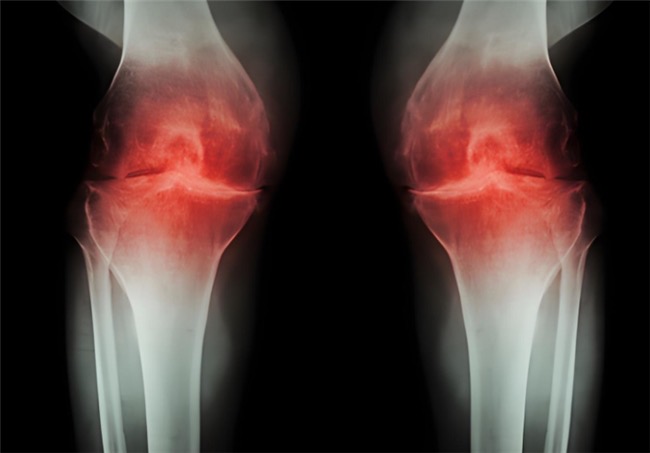

骨关节炎作为常见的关节退行性疾病,困扰着众多中老年人乃至长期劳损的人群。患者不仅会频繁遭遇关节疼痛、肿胀、僵硬等不适,随着病情发展,还可能出现活动受限、关节变形,进而影响走路、上下楼等日常行为,让生活质量大打折扣。更令人担忧的是,骨关节炎的病程一旦进入中晚期,治疗难度和痛苦都会明显增加。因此,及早干预至关重要。而氨基葡萄糖就是临床常用的治疗药物之一,但它还有盐酸和硫酸氨基葡萄糖之分,到底盐酸和硫酸氨基葡萄糖的作用与功效有什么不同?骨关节炎患者如何选择呢?

盐酸和硫酸氨基葡萄糖胶囊都是氨基葡萄糖类药物,能为关节软骨提供合成原料,在促进软骨基质的修复与再生的基础上,补充关节滑液以减少摩擦,同时通过抑制关节腔内的炎症因子,从多个方面帮助延缓骨关节炎的进展[1],但它们在临床疗效上却存在一定差异。

根据国际医学四大期刊之一《美国医学会杂志》上发布的一项研究表明,硫酸氨基葡萄糖在缓解膝骨关节炎疼痛、改善关节活动功能方面,效果优于盐酸氨糖等33种骨关节炎常用药[2]。还有相关研究显示,硫酸氨基葡萄糖不仅能延缓关节间隙变窄,还能从根源改善关节结构、减缓磨损。而盐酸氨基葡萄糖在这一关键指标上的效果尚未明确。因此,在关节保护的“确切性”上,硫酸氨基葡萄糖显然更具优势。